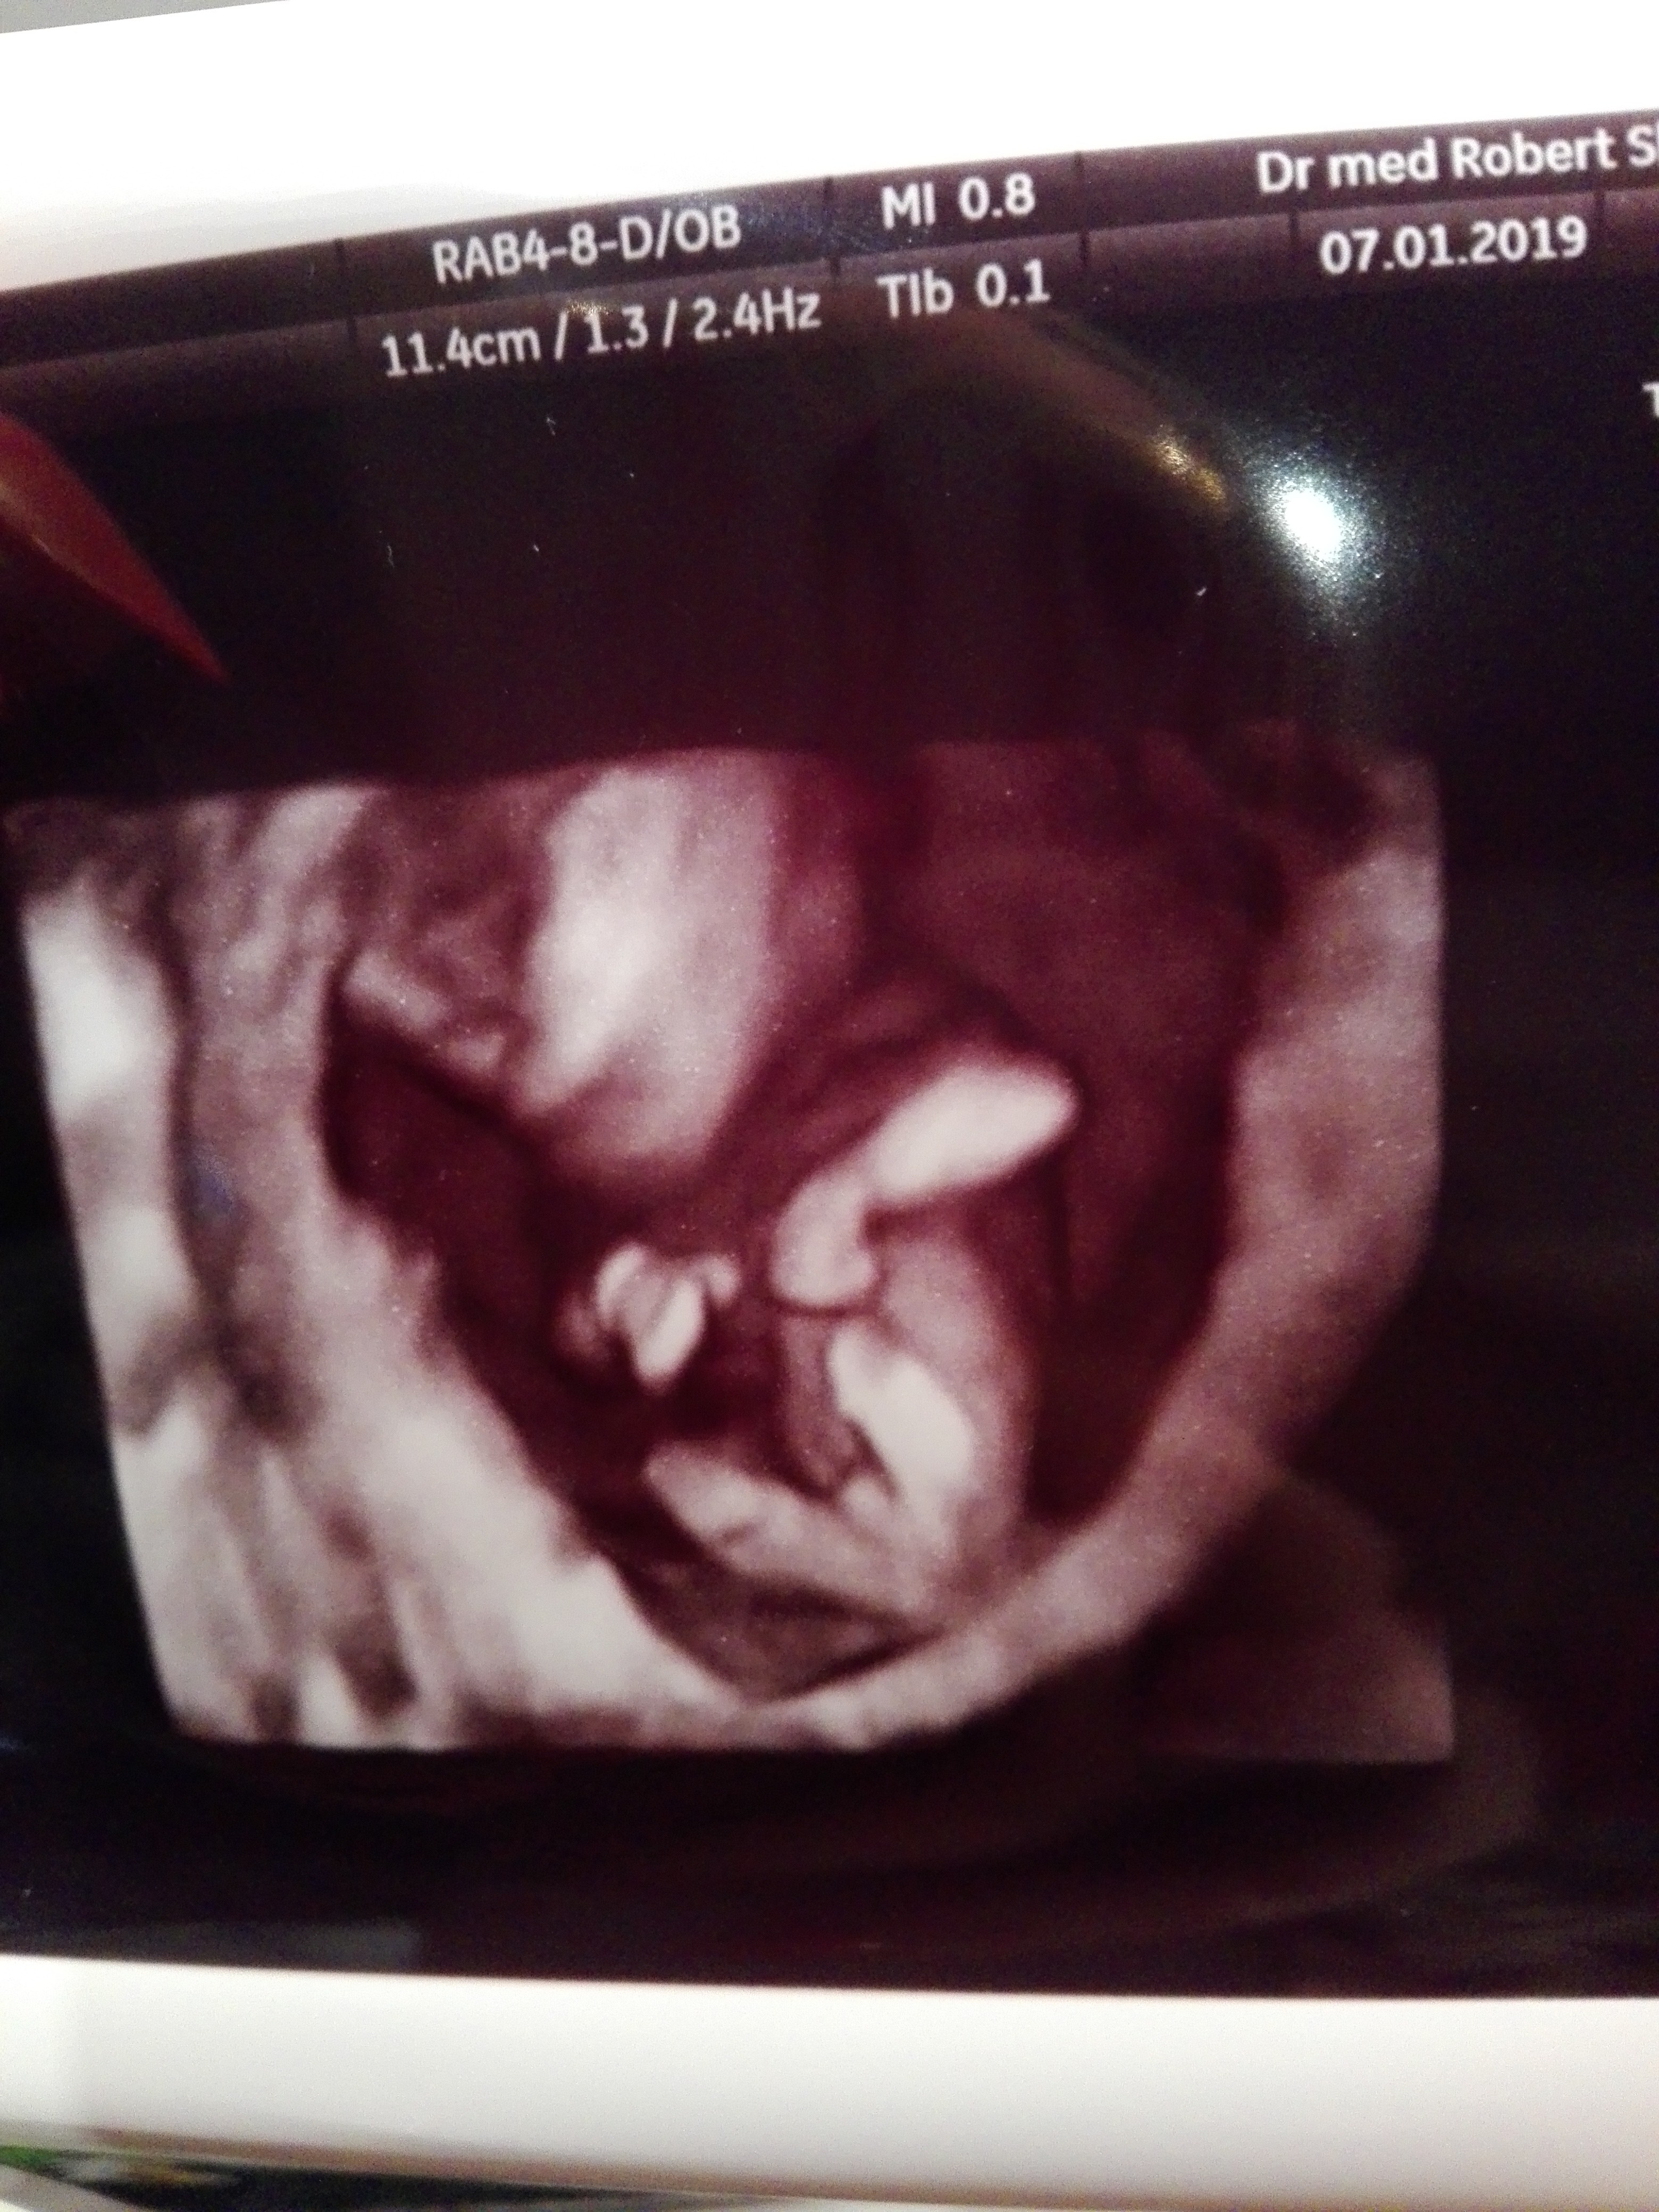

Ja już po. Dziecko zdrowe, wszystko jak najbardziej ok. Nie mam już złudzeń na dziewczynkę :( w załączniku dowód kurde ale kilka % jest, że odpadnie to tego się trzymajmy heh

Załączniki

• IMG_20190107_184552.jpg

IMG_20190107_184552.jpg

2,1 MB · Wyświetleń: 155